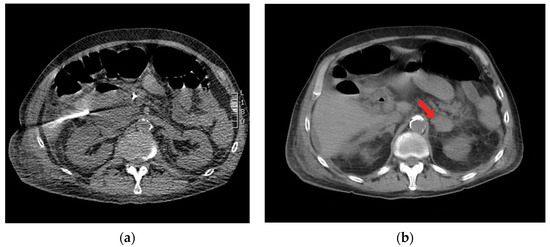

Figure 2. Axial computed tomography (CT) imaging shows (a) percutaneous insertion of a 19 Gauge needle for drainage of periduodenal collection, and (b) left-sided adrenal hematoma with surrounding stranding of peri-adrenal fat (red arrow).

During the CT-guided drainage, after the needle punctured the collection and a wire was placed, the patient developed sudden onset left back pain and hypertension. CT imaging revealed a spontaneous left adrenal gland hemorrhage (Figure 2b). The drainage procedure was completed by inserting a 10 French drain over the wire and formed within the central aspect of the collection; turbid fluid was aspirated (Figure 3). After the procedure, the patient was observed in the CT suite. Intravenous (IV) analgesia was administered resulting in pain relief, and serial CT imaging with IV contrast showed stability of the left adrenal hemorrhage. Intravenous antihypertensives were administered to manage the acute hypertension. The patient was subsequently hospitalized for pain and hypertension management, secondary to spontaneous adrenal hemorrhage.

Figure 3. Axial (a) and coronal (b) computed tomography (CT) imaging shows periduodenal drain placement with a 10 French catheter.